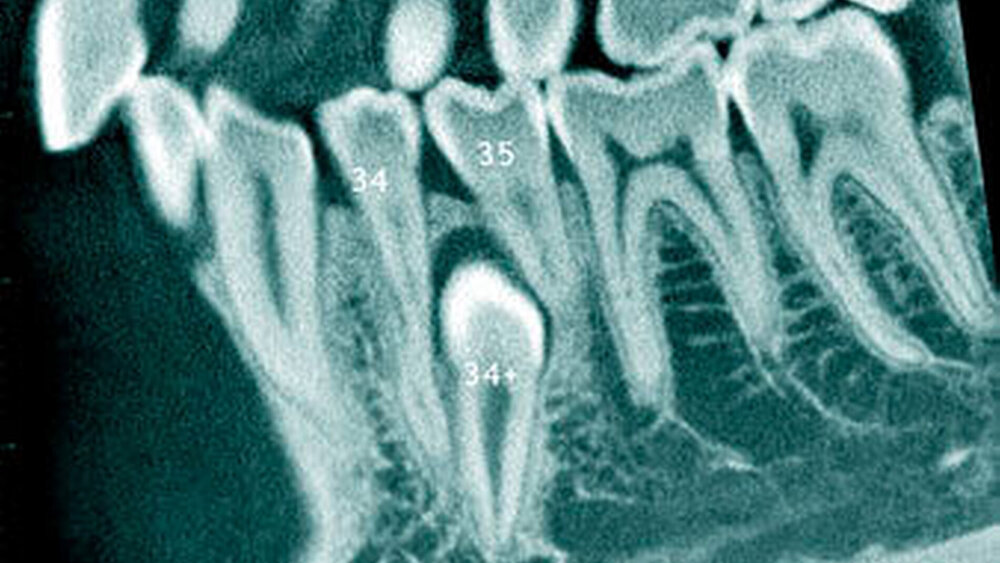

Überzählige Zähne können einzeln oder multipel auftreten [von Arx, 1990; Rajab Hamdan, 2002; Fernández Montenegro et al., 2006; Liu et al., 2007; Gündüz et al., 2008; Ferrés-Padró et al., 2009; Hyun et al., 2009]. Einzelne überzählige Zähne treten in 65,8 bis 80,5 Prozent, doppelte in 14,5 bis 27,7 Prozent und multiple in 0,6 bis 8 Prozent der Fälle auf [Rajab Hamdan, 2002; Fernández Montenegro et al., 2006; Liu et al., 2007; Ferrés-Padró et al., 2009; Hyun et al, 2009; Mossaz et al., 2014]. Einzelne oder doppelte überzählige Zähne finden sich typischerweise in der Oberkieferfront [Rajab Hamdan, 2002; Fernández Montenegroet al., 2006; Mossaz et al., 2014]. Multiple überzählige Zähne werden vor allem im Prämolarenbereich des Unterkiefers gefunden [Abbildung 4; YUSOF 1990, Ferrés-Padróet al., 2009; Wang Fan, 2011]. Multiple überzählige Zähne sind zudem oft mit anderen Erkrankungen oder Syndromen assoziiert, dazu gehören Lippen-Kiefer-Gaumenspalten, die cleidokraniale Dysplasie oder auch das Gardner-Syndrom. Bei Patienten mit einer Lippen-Kiefer-Gaumenspalte wird vermutet, dass sich die überzähligen Zähne aus der Fragmentierung der dentalen Lamina bei der Spaltbildung ergeben [Garvey et al., 1999; Wang Fan, 2011].

Überzählige Zähne werden nach ihrer Lage im Zahnbogen und auch aufgrund ihrer Morphologie eingeteilt. Basierend auf der Lage unterscheidet man bei überzähligen Zähnen zwischen Mesiodens (Oberkiefer median), zwischen den zentralen Inzisiven (Abbildungen 5 und 6), einem zusätzlichen Schneidezahn (zentral oder lateral), Eckzahn, Prämolar (Abbildung 7), Paramolar und Distomolar (Abbildungen 8). Mesiodentes werden am häufigsten dia- gnostiziert, wobei Prozentsätze zwischen 38,8 Prozent bis 86,3 Prozent der überzähligen Zähne in der Literatur zu finden sind [Salcido-García et al., 2004/38,8 Prozent, Fernández Montenegro et al., 2006 /46.9 Prozent; Mossaz et al., 2014/48.5 Prozent; Ferrés-Padró et al., 2009/53.2 Prozent; Schmuckli et al., 2010/75 Prozent; Rajab Hamdan 2002/83.2 Prozent; Liu et al., 2007/86.3 Prozent]. Überzählige Prämolaren und seitliche Schneidezähne sind die zweithäufigste Gruppe der überzähligen Zähne. Überzählige Eckzähne, Paramolaren und Distomolaren dagegen gelten als eher selten [Rajab Hamdan, 2002; Salcido- García et al., 2004; Liu et al., 2007; Ferrés-Padró et al., 2009; Schmuckli et al., 2010; Mossaz et al., 2014]. Einzig eine Spanische Gruppe [Fernández Montenegro et. al., 2006] berichtete, dass Paramolaren und Distomolaren insgesamt relativ häufig seien (18 Prozent, beziehungsweise 5,6 Prozent). Überzählige Zähne kommen im Ober- und Unterkiefer vor, wobei sich überzählige Schneidezähne in der Regel im Oberkiefer, überzählige Prämolaren sich dagegen eher im Unterkiefer befinden [Fernández Montenegro et al., 2006; Ferrés-Padró et al., 2009; Mossaz et al., 2014]. Überzählige Molaren wiederum treten normalerweise im Oberkiefer auf [Cassetta et al., 2014; Kaya et al., 2014].

Überzählige Prämolaren zeigen eine identische Zahnform. Überzählige Zähne in anderen Regionen des Ober- und Unterkiefers haben dagegen keine charakteristische Morphologie [Fernández Montenegro et al., 2006; Gündüz et al., 2008; Hyun et al., 2009; Schmuckli et al., 2010; Mossaz et al., 2014].

Dagegen haben überzählige Prämolaren in der Regel eine geneigte oder normale Eruptionslage [Mossaz et al., 2014]. Überzählige Zähne können normal durchbrechen oder bleiben retiniert beziehungsweise teilretiniert. Frühere Studien berichteten, dass zwischen 15 Prozent [Tay et al., 1984) und 34 Prozent [LIU et al., 1995] der überzähligen Zähne erst im bleibenden Gebiss durchbrechen. Im Gegensatz dazu eruptieren 73 Prozent der überzähligen Zähne bereits im Milchgebiss [Humerfelt et al., 1985}. Nicht-durchgebrochene überzählige Zähne können asymptomatisch bleiben und werden erst zufällig während einer routinemäßigen Zahnkontrolle auf einem Röntgenbild – in der Regel einer intraoralen Aufnahme – diagnostiziert. Überzählige Zähne werden jedoch auch dann entdeckt, wenn ein bleibender Zahn in seinem Durchbruch entweder verzögert oder in seiner Lage verschoben ist.